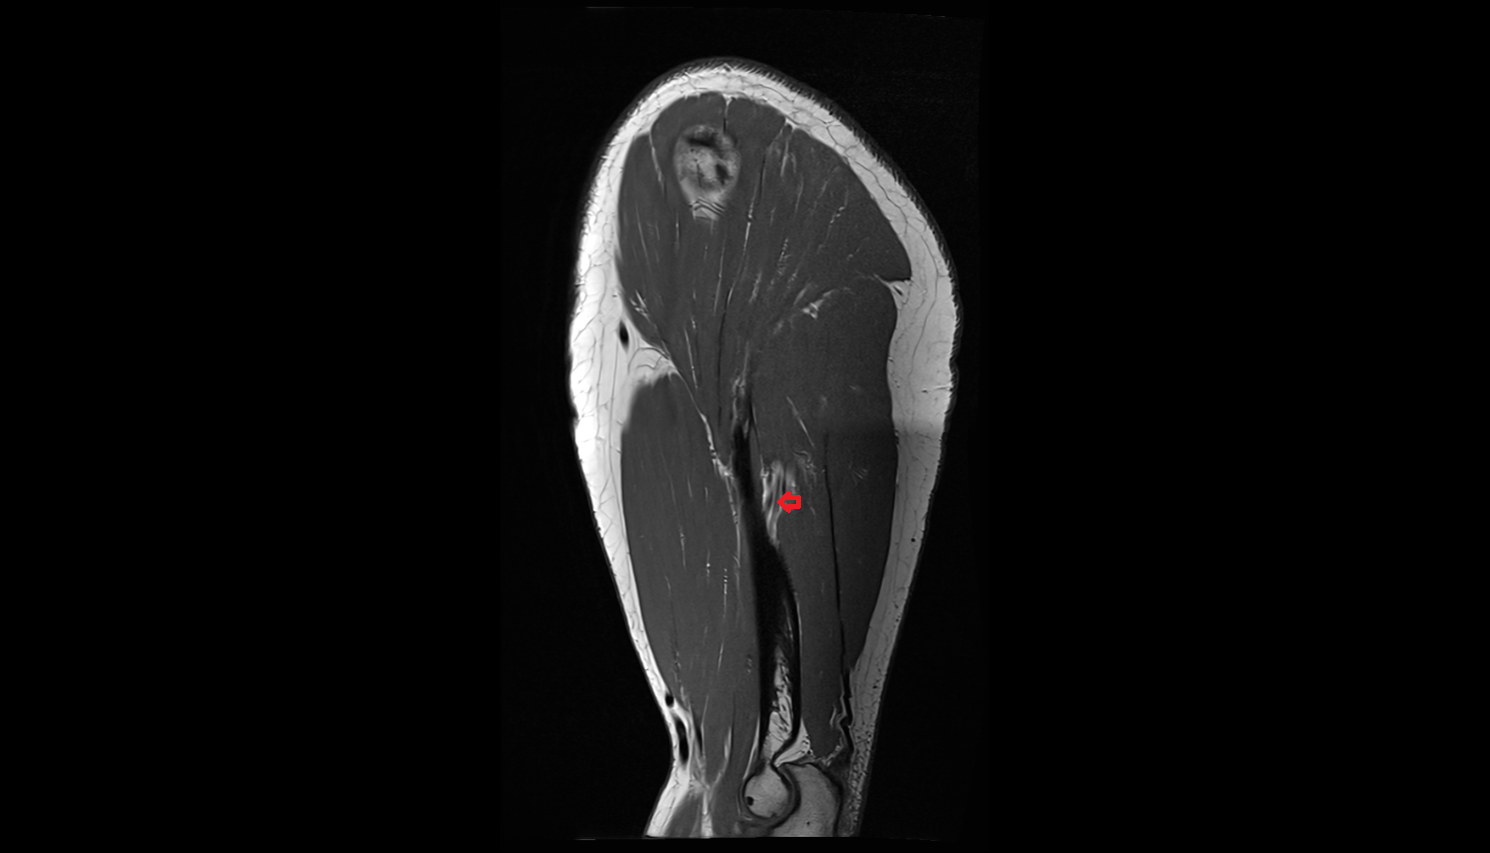

- Fetal thigh